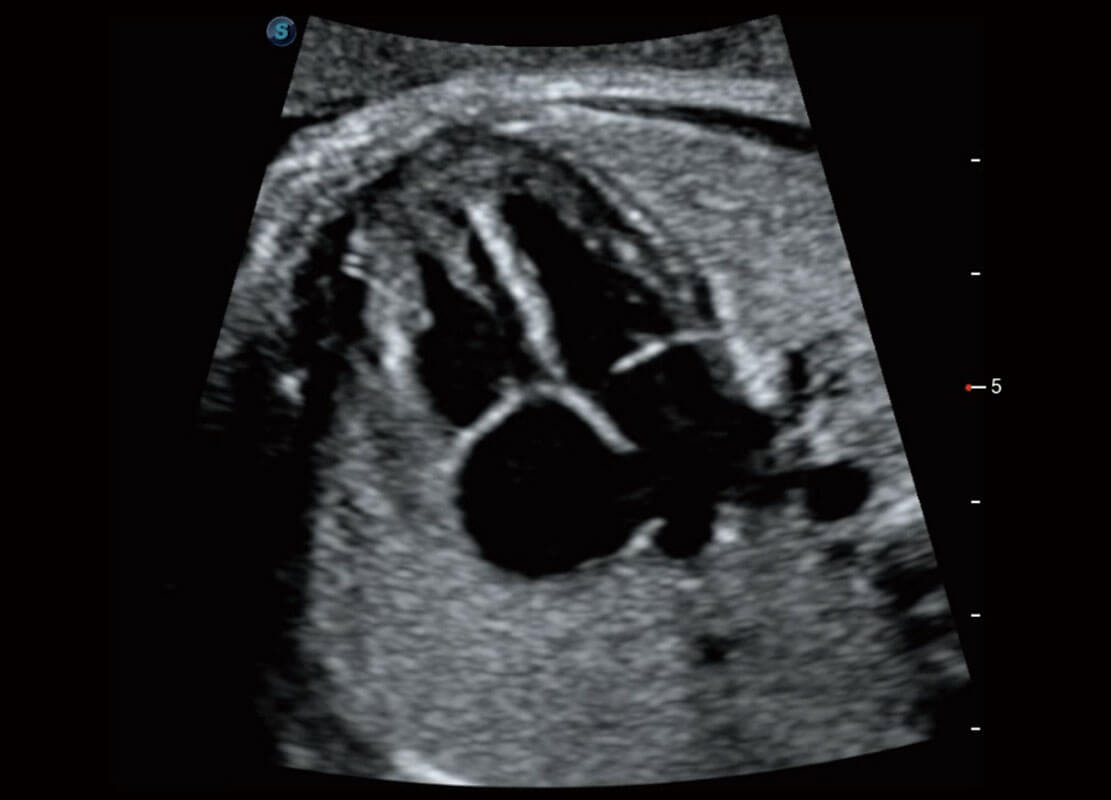

生殖健康

P60优异的图像质量搭载专科探头,在妇科基础疾病的诊断、卵泡生长的监测、输卵管通畅情况的判别等方面为您提供生殖应用方案。

• 腔内妇科-宫腔分离

• 腔内妇科-卵巢